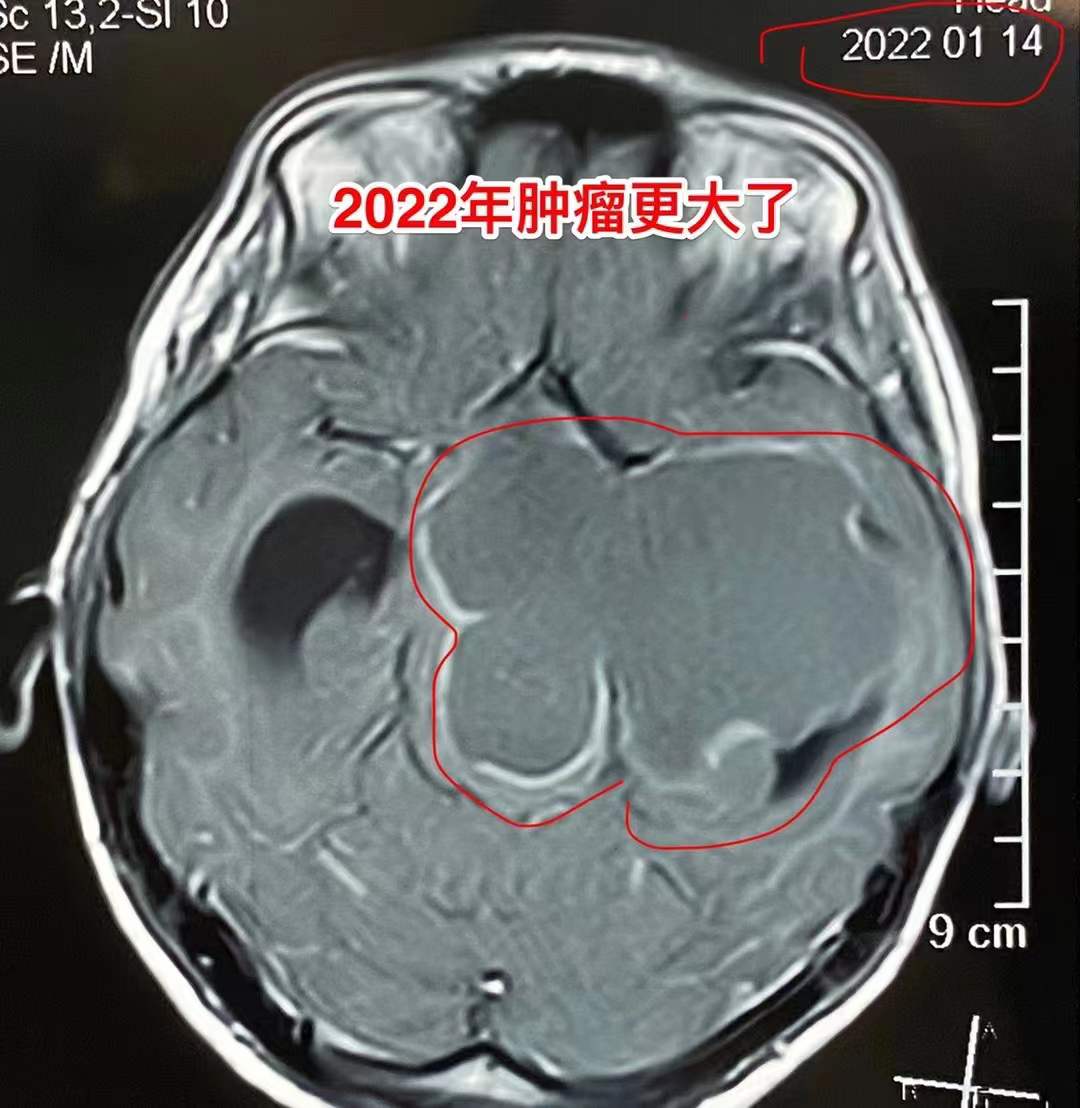

到2022年一月患儿行走都有困难了,复查磁共振见图5、图6。肿瘤进一步长大了。从图8可以看出肿瘤有钙化,是典型的造釉细胞型颅咽管瘤。

图五

图六

对于颅咽管瘤,最有效的治疗是做手术切除肿瘤。中药治疗效果不确切,吃了三年中药,肿瘤体积增加了好几倍,即使再考虑做手术,其风险肯定也增加了不少。